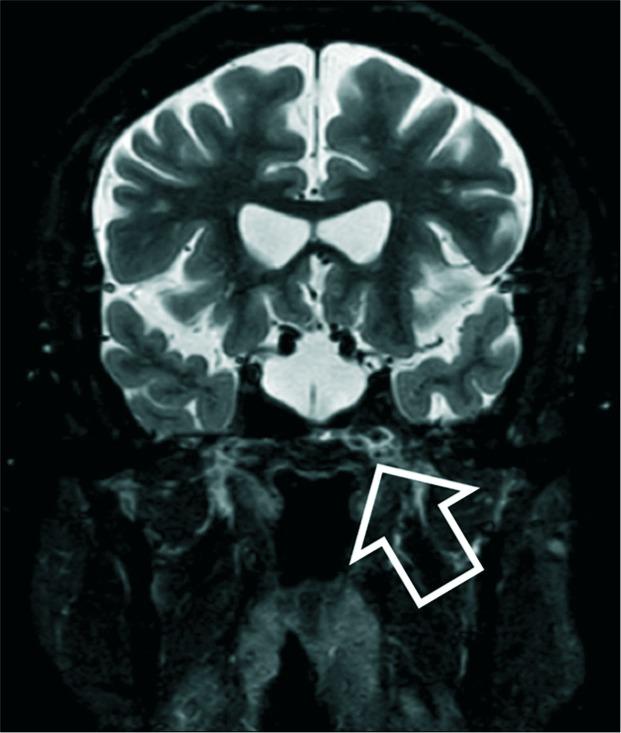

A 56-year-old man presenting with deficits of both visual acuity and visual fields in the setting of radiological ESS without associated optic chiasm prolapse is discussed. He underwent endoscopic endonasal chiasmapexy with gradual improvement of his visual function over the following 6 months.

本文讨论了一名56岁男性,其在影像学检查显示ESS且无相关视交叉脱垂的情况下出现视力和视野缺陷。他接受了鼻内镜下视交叉固定术,在接下来的6个月里视觉功能逐渐改善。